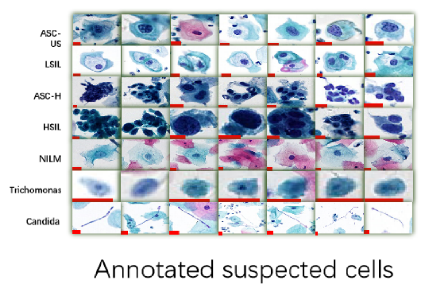

Artificial intelligence is applied based on Deep Convolutional Neural Networkd (DCNN) to retrospectively

analyze cervical liquid-based cytology samples to confirm its feasibility in clinical practice.

Whole-slide images annotation,

suspected cell detection model training

Efficient method to detect suspicious

cells in WSI, validate model with a large

number of slides

High sensitivity validated in clinical

practice for different lesion types

Graded lesion cells, count cell quantity

automatically